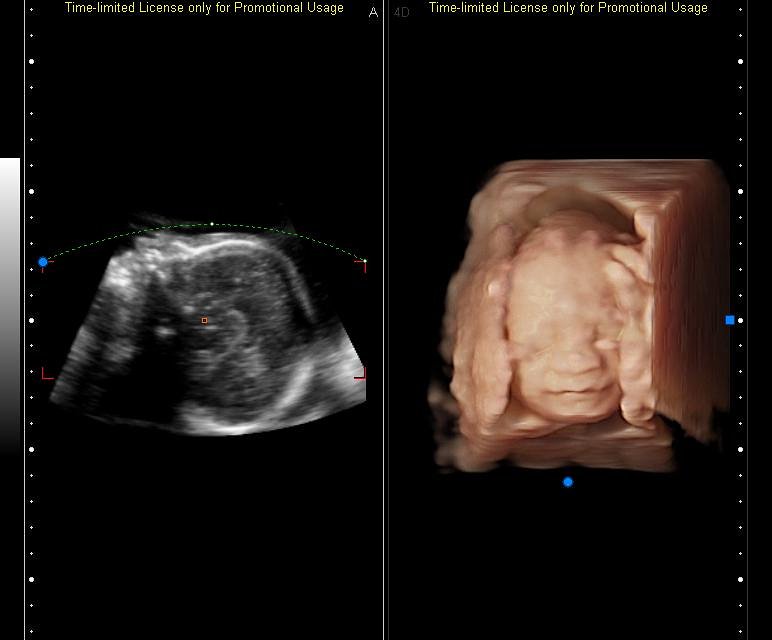

Gambar Usg 6 Bulan

Kenali Cara Membaca Hasil USG Untuk Tahu Kondisi Bayi - Ibupedia Bagaimana Cara Membaca Hasil USG? • Hello Sehat Pergerakan Janin umur 6 bulan!!! Hasil USG - YouTube USG 3D HAMIL 25 MINGGU ( 6 bulan) | SEHAT SELALU CALON ANAKKU - YouTube 5 Langkah Membaca Hasil USG yang Bisa Bunda Pelajari Ini Dia Cara Membaca Hasil USG dengan mudah - Mamapapa.id % Story of My Journey: USG Kehamilan 6 Minggu Cara Membaca Hasil USG yang Benar, Wajib Tahu! Ini Rata-Rata Berat Janin 5 Bulan - Alodokter usg 6 minggu USG 4 Dimensi Kehamilan Halaman 1 - Kompasiana.com Penyebab janin dalam kandungan menghilang USG 4 Dimensi 6 bulan 2 Minggu - YouTube Penjelasan di Balik Bayi Bisa Tersenyum di dalam Kandungan janin 6 bulan hamil 6 bulan kehamilan 6 bulan perkembangan https://babyologist.com/blog/mengapa-bayi-lebih-aktif-di-malam-ha… | Tips, Gynecology, Pandora screenshot USG [2] : Enam Belas Minggu Enam Hari – Jejak-jejak yang Terserak Kapan Denyut Jantung Janin Bisa Terdeteksi? | HonestDocs USG 4 Dimensi Kehamilan Halaman 1 - Kompasiana.com USG Pertama Kehamilan 6 Minggu | KISAH KASIH BUNDA USG 2 Dimensi janin umur 6 bulan - YouTube Usg hamil 6 week 4 day (menurut usg) 6week 5day (menurut hph USG [6] : 34 Minggu 2 Hari – Jejak-jejak yang Terserak foto 4 D kehamilan 6 bulan dg usg… - salsabila obgyn clinic | Facebook Cara Membaca Hasil USG yang Benar, Wajib Tahu! banyak yg mengalami ga? 7 minggu usg belum terluhat janin sama sekali hanya - IbuHamil.com Ukuran Kantong Janin 6 Minggu Yang Normal Dan Tidak Bermasalah - Hamil.co.id ALBUM KELUARGA: USG 4 DIMENSI BAYI 6,5 BULAN (ADIK DZIKRI) Informasi Kehamilan Sehat Bulan 6 : Perlukah USG 3 dan 4 Dimensi? - Semua Halaman - Nakita Tiga Hal yang Jarang Orang Ketahui jika Ibu Hamil Lakukan USG 4D - Tribun Jabar usg 6 bulan 3 dimensi 12 Oktober 2016 - YouTube Gambaran Hasil Usg Kehamilan 5 Minggu Yang Perlu Diperhatikan - Hamil.co.id share hasil usg uk 6 bulan ? - IbuHamil.com Begini Kondisi Janin di Usia Kehamilan 1 sampai 6 Minggu Kehamilan - Tribun Sumsel USG 3D dan USG 4D, Apa Bedanya? Mana yang Lebih Baik? 6 Hal yang Harus Dipersiapkan saat Pertama Kali Melakukan USG | Popmama.com Evan Reisha - Kontrol Kandungan Ke-6 (Trimester 2-3, 27W6D) JANIN BELUM TERLIHAT SAAT USG? JANGAN KHAWATIR, MOMS! - susistory Lakukan USG Saat Trimester Kedua, Mama Bisa Tahu 6 Hal Penting Ini | Popmama.com Manjakani Kanza Asli Aceh: Hasil Usg Usia Kehamilan 6 Bulan Inilah Alasan Ibu Hamil Perlu Melakukan USG Kehamilan Hasil USG 6 bln, JK cewe??? - IbuHamil.com Perkembangan Kehamilan Si Kembar 15 Minggu 5 Hari – cizkah.com Tag: bayi - Ngeri! Pedofil Incar Janin Belum Lahir, Bukti Foto USG Gegerkan Pengadilan - Tribun Manado Pentingkah USG 4 Dimensi? - Mommies Daily USG [1] : Enam Minggu Lima Hari – Jejak-jejak yang Terserak Usg 4D 25 minggu/ 6 bulan. IT’S A BOY!! - YouTube Cara Melakukan USG 2 Dimensi yang Benar dan Tepat - Bidanku.com Cara Membaca Hasil USG, Simak Ini Panduannya Viral, Rekaman USG Bayi Kembar Bertengkar dalam Rahim - Citizen6 Liputan6.com Pengalaman Hamil Kembar - The Urban Mama Hamil Setelah Keguguran - Mommies Daily Janin 6 Bulan : Tumbuh kembang - Yang perlu dilakukan (Kerjanya) Jumlah Bayi Kembar yang Lahir Tak Sesuai Hasil USG? Ini Penjelasan Dokter Gambaran Hasil Usg Kehamilan 6 Minggu Yang Normal - Hamil.co.id Diary Kehamilan: Cerita Kehamilan Pertama, Pertama Tahu Hamil – ranselriri Aryani Fitriana Umumkan Hamil Anak Kedua Lewat Foto Hasil USG! - Semua Halaman - Nakita Catatan Calon Ayah # 6: USG Kehamilan | WebLog Andika Priyandana Hasil USG 4 Dimensi Ini Menyeramkan - Health Liputan6.com Wajah & Kelamin Bayi 6 Bulan - Halaman 2 - IbuHamil.com USG 4 Dimensi Kehamilan Halaman 1 - Kompasiana.com Pamerkan Perut Rata Saat Hamil 6 Bulan, Kisah Wanita Ini Viral - Parenting Fimela.com Adib’s Mom: USG 4D Usia Kandungan 6 Bulan Kehamilan Bulan Keenam | New Mom’s Diary 10 Fakta Janin 37 Minggu Yang Harus Diketahui Oleh Calon Ibu - Cintai Hidup USG 4D - Video Perbedaan USG 4D, 3D dan 2D yang Perlu Anda Ketahui | theAsianparent Indonesia PT. Setia Manggala Abadi : “Hasil pengambilan USG dengan usia kehamilan ibu 6 bulan. Pengambilan gambar USG menggunakan USG SOGATA SG9 4D & Color Doppler #sogata… https://t.co/pDqV007DiP” Cara Membaca Hasil USG, Simak Ini Panduannya 6 month Pregnancy | Blognya Ayu USG Janin 6 Bulan - 25 Minggu. Kelihatan Wajah & Jenis Kelamin. - YouTube Pengalaman saat Alami Kehamilan Kosong (Blighted Ovum) Halaman all - Kompasiana.com Perempuan Ini Mengaku Hamil 6 Bulan di Usia 70 Tahun Halaman all - Kompas.com Tahap Perkembangan Hamil 6 Bulan | Redaksi Cepat FDA Peringatkan Ibu Hamil Jauhi USG Buat Kenang-kenangan - Health Liputan6.com Masa Perkembangan dan Posisi Janin Usia 6 Bulan | Prenagen 6 bulan – Masrafa.com 3 Cara Membaca Hasil USG yang Benar, Biar Nggak Salah Kaprah | merdeka.com Story of My Journey: USG Kehamilan 19 Minggu Hamil 5 Minggu: Pentingnya Pemeriksaan Kandungan dan USG RutinElla | MamiBuy Janin 6 Minggu Ini Berpose Jari V - Sriwijaya Post Ini Waktu Yang Ideal Untuk Melakukan USG 4 Dimensi Saat Hamil - Semua Halaman - Nakita Sedang hamil, ini 10 foto USG yang kerap dipamerkan Shandy Aulia Moms, Ini Penyebab dan Tanda Hamil Bayi Berukuran Kecil - kumparan.com Membaca hasil USG pada pemeriksaan kehamilan | Darwis untuk Indonesia Kehamilan 23 Minggu | KISAH KASIH BUNDA Foto: Perkembangan Janin dalam Kandungan dari Bulan ke Bulan - kumparan.com Keluarga JagoAN: Kehamilan Bulan ke 6 (Minggu ke 21 - 24) USG 4 bulan – pratiwanggini.net Kapan Ibu Hamil Sebaiknya Melakukan USG? USG 4D - Video Perbedaan USG 4D, 3D dan 2D yang Perlu Anda Ketahui | theAsianparent Indonesia USG 6 bulan kehamilan ||cewek/cowok…??? - YouTube Sharing Hasil USG 6 bulan - IbuHamil.com Cari Tahu Berat Janin 6 Bulan yang Normal di Sini - Alodokter Ciri Kehamilan 6 Minggu Yang Sehat, Harap Hati-hati Mandi Air Hangat! Netizen Peringatkan Shandy Aulia Karena USG Tiap Minggu, Bahayakah? Manfaat USG untuk Ibu Hamil dan Janin - Ibupedia Usg 4 dimensi, Klinik Metro Medika di perumahan Metro Permata I, jl Metro Permata utama blok E2 no 3 karang tengah, Ciledug., Tangerang (2020) Dinamika Hidupku: Oktober 2013 Aneh, Hamil 6 Bulan Perut Perempuan Ini Tetap Rata Kehamilan Pertamaku – Persiapan Calon Ibu Menjelang 7 Bulan - F-News Kehamilan 6 Bulan: Keluhan Apa yang Anda Rasakan?